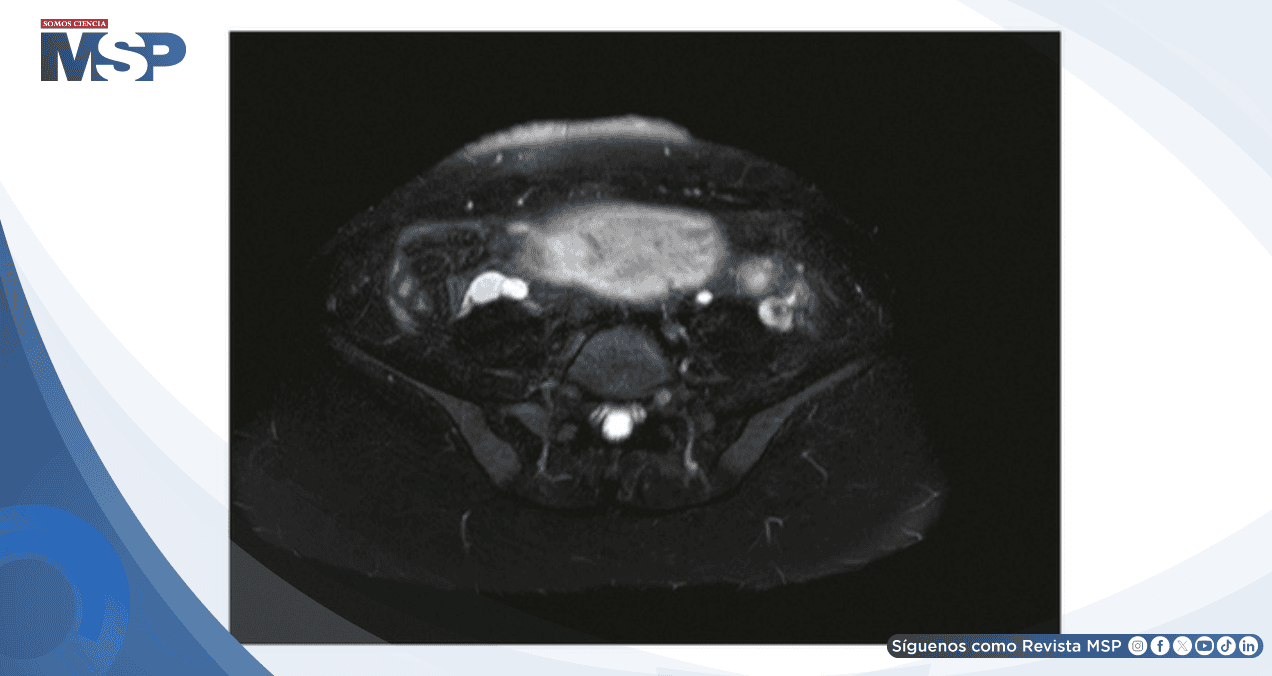

Se realizó resonancia magnética (RM) y venografía por resonancia magnética (MRV) de abdomen y pelvis sin contraste, que evidenció:

Apendicitis aguda no complicada con un apéndice de 12 mm y cambios inflamatorios periapendiculares, sin signos de perforación.

Pelviectasia derecha leve (4,9 mm).